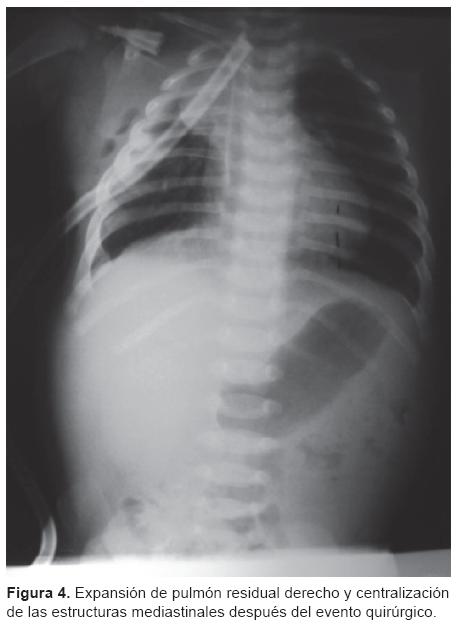

La paciente evolucionó de forma favorable. El pulmón derecho residual presentó una buena expansión posquirúrgica y se centralizaron las estructuras mediastínicas (Figura 4). Se retiró la sonda de la toracotomía al sexto día después de la cirugía. También se corrigieron la sepsis y las alteraciones hematológicas.

Por lo anterior, en este caso se decidió el tratamiento quirúrgico, mismo que se llevó a cabo de manera exitosa con una evolución favorable, presentando una buena expansión del pulmón residual derecho y la corrección en la posición de las estructuras medias-tínicas. Únicamente presentó hipertensión pulmonar leve como secuela.